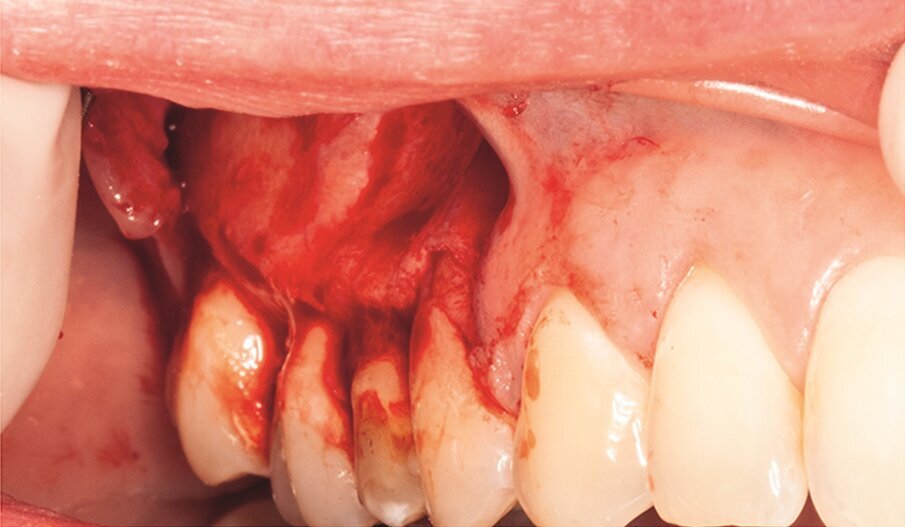

Under local anaesthesia, a full-thickness mucoperiosteal‑ap was reflected, providing visualisation of the buccal bone (Fig. 2g), and the printed template was used to mark the cortical window (Fig. 2h), which was cut with a Piezotome CUBE LED handpiece, and the separated instrument was exposed (Fig. 2i) and removed (Fig. 2j). After apicectomy, retro-preparation was done using ultra sonic tips (ACTEON) and sealed with TotalFill BC RRM Fast Set Putty (FKG) (Fig. 2k). The ‑ap was sutured using 5/0 prolene suture material (Fig. 2l). The sutures were removed 72 hours postoperatively. After two years the patient came to our office for a follow-up radiograph, the tooth was asymptomatic and in function (Fig. 2m).

Fig. 2g: Full-thickness mucoperiosteal flap reflected.

Fig. 2h: The template was adjusted and the limits of the cortical window were marked in the bone.